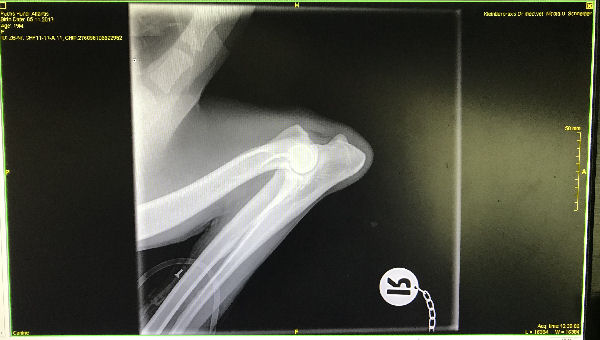

Atlantis - ED-Röntgen

img_5247 (1)-Atlantis-ed-rechts